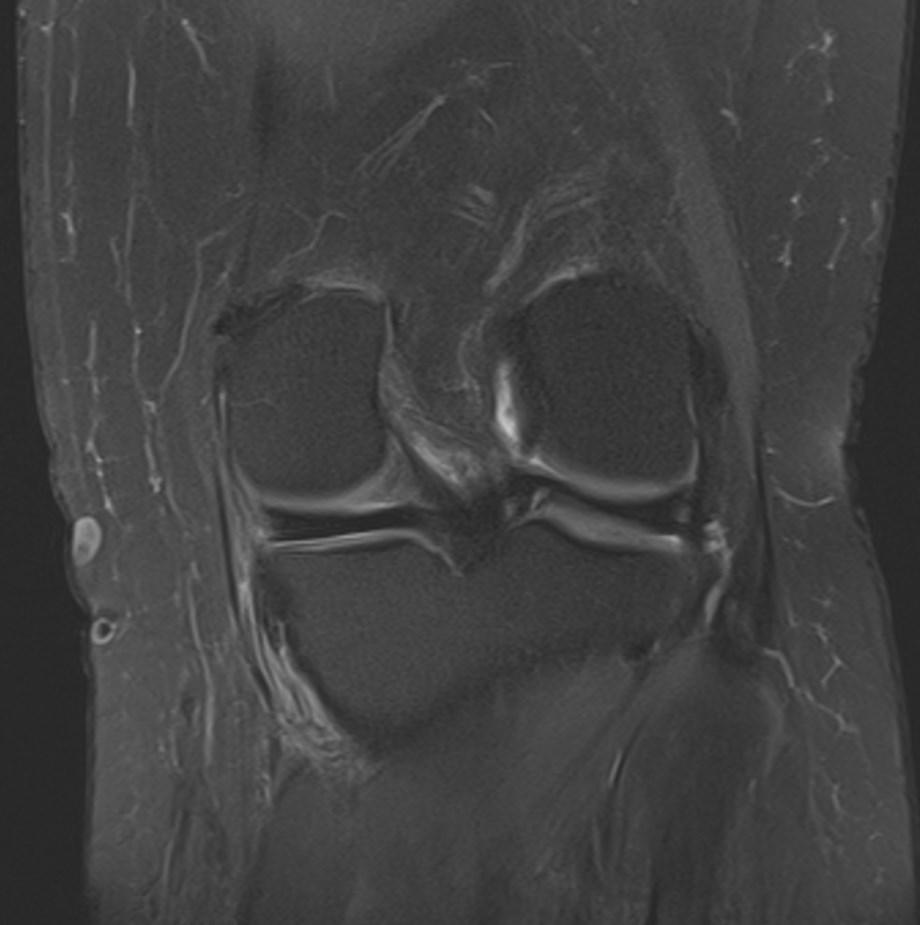

*32-year-old female present with pain along the proximal medial tibia.

What is the most likely diagnosis?

Answer: Pes anserinus bursitis

MR images showed edema-inflammation of the pes anserinus bursa which is located at the medial aspect of the knee deep to the pes anserinus tendons.

Pes anserinus bursitis refers to symptomatic inflammation of the pes anserinus bursa which is located at the medial aspect of the knee deep to the pes anserinus tendons.